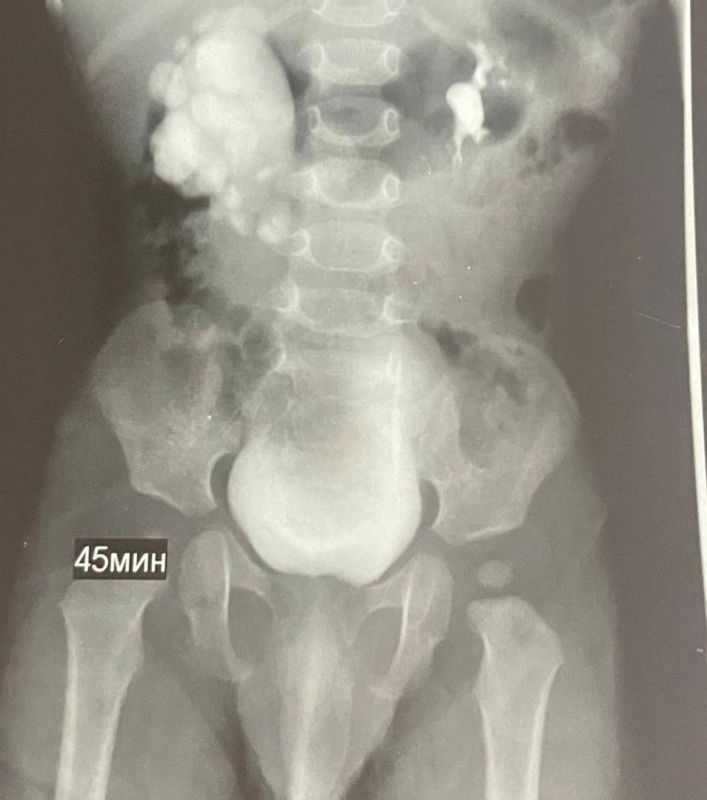

У ребёнка ещё до рождения заметили проблемы с почкой на УЗИ, а после появления на свет состояние стало ухудшаться — диагностировали гидронефроз. При этом опасном состоянии почка могла бы перестать функционировать.В ноябре врачи ставропольской больницы...